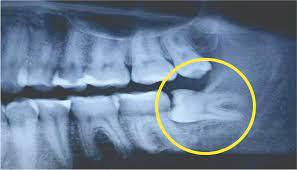

Sau khi có kết quả chụp X-Quang, bác sĩ chẩn đoán do 1 răng khôn của Lin mọc ngầm và lệch nên mới dẫn đến tình trạng đau nhức. 3 chiếc răng khôn khác cũng bị ảnh hưởng.